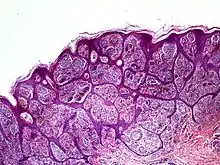

Nevoid melanoma is a cutaneous condition that may resemble a Spitz nevus or an acquired or congenital melanocytic nevus.[1]